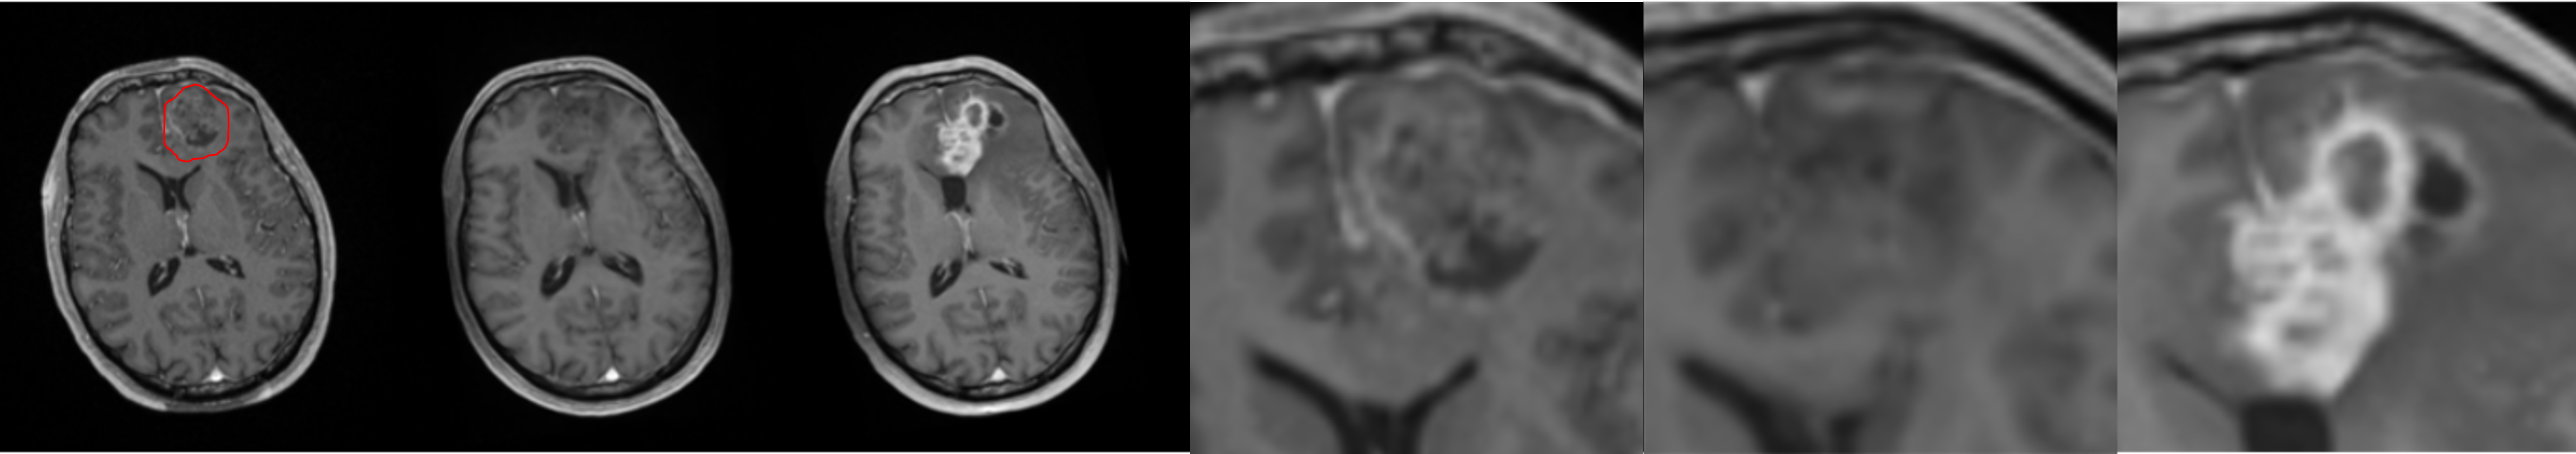

To further illustrate the model’s performance we retained only the pred 2-class model, as it reflects a realistic use case. We present several generated examples in Fig. 4. The first row corresponds to the highest local SSIM score (0.71), depicts a patient who underwent total resection, where tumor progression is minimal. We observe that the model fails to predict the hyper-intensity in the periphery of the tumor (T1-enhancement) in comparison to the ground truth. In contrast, the last row corresponds to the lowest SSIM score (0.02), making it an edge case. We observe that the model generally failed to predict T1-enhancement localized to the tumor area; however, it succeeded in predicting the necrotic area.